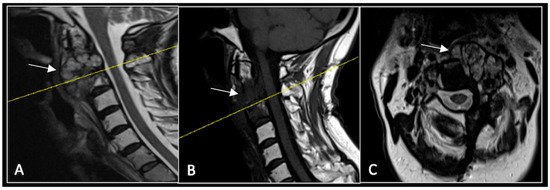

A 73-year-old male presented with an eight-month history of neck pain that was exacerbated on lying flat. He denied any symptoms of myelopathy and radiculopathy. He did not have any constitutional symptoms of malignancy. Past medical history included hypertension, renal cysts, and an ascending thoracic aneurysm. Examination was unremarkable. Diagnostic whole-spine MRI imaging demonstrated a large lobular mass localised to the cervical spine (Figure 2). Biopsy confirmed a conventional chordoma, and he underwent separation surgery followed by adjuvant proton beam therapy. Postoperative surveillance imaging at 12 months demonstrated stable disease (Figure 3).

Figure 2.

MRI demonstrating a destructive lobular lesion localised to the C2 vertebra (chordoma) (arrow). There is significant left-sided extension into the paravertebral tissues laterally and epidural space centrally with indentation of the cord. The yellow line on the sagittal images denotes the level at which the corresponding axial section was obtained. (A) T2-W sagittal; (B) T1W sagittal; (C) T2W axial.